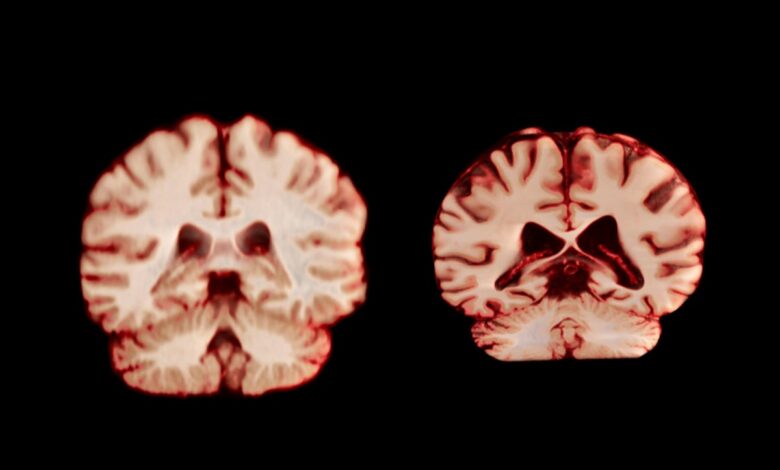

A healthy brain (left) and a brain affected by Alzheimer’s disease.

During ageing, men experience a greater reduction in volume across more regions of the brain than women do, according to a longitudinal study published today in the Proceedings of the National Academy of Sciences. The authors suggest this means that age-related brain changes do not explain why women are more frequently diagnosed with Alzheimer’s disease than men are.